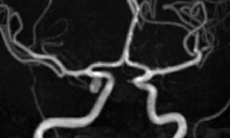

Liệt dây thần kinh số 7 ngoại biên

Người dân cần che chắn, giữ ấm vùng mặt khi ra ngoài để phòng ngừa liệt mặt mùa đông. Hình minh họa